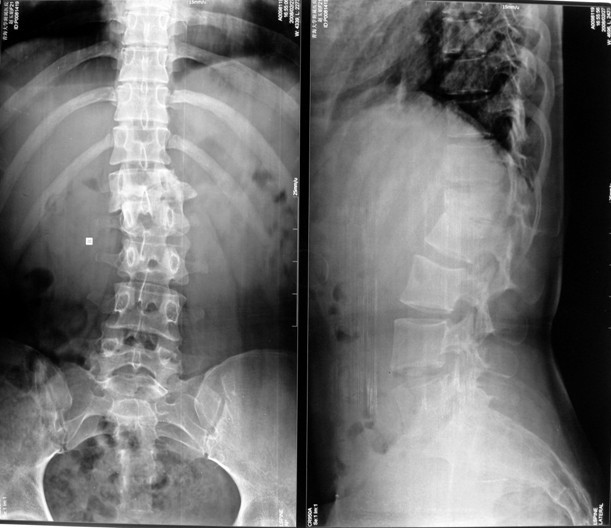

本组46例中男28 例,女18 例。年龄17~67岁,病程6 个月~7年,平均11.3 个月。本组患者均为 L1~S1腰段结核。病灶累及2 个椎体31例(L1-2 6例, L2-3 8例,L3-4 10例,L4-5 5例,L5-S1 2例),3 个或3 个以上椎体15例。合并腰大肌脓肿23列,所有患者均有腰背部疼痛,活动受限,双下肢感觉麻木19例,会阴部感觉减退12例,双下肢肌力减弱12例,腱反射减弱12例,术前后凸角(Cobb 角) <30°者12例, 30°~60°者28 例, >60°者6 例,Cobb角平均32.3°4例患者是二次手术。术前均行X线片、CT或者MRI检查。术后病理检查确诊为脊柱结核。

本组手术用时间3~4h , 平均3.5h 。术中出血300~500ml , 平均约350ml 。术后症状完全缓解,无神经功能障碍加重等并发症,1例营养差的老年患者伤口出现窦道,1例因肝功能差,术后未口服抗痨药,伤口出现窦道,经换药后二期愈合,其余病例伤口均一期愈合。马尾神经受损的患者术后基本恢复正常。术后一周后凸角平均 5.4°后凸畸形平均矫正90%以上, 最终后凸角平均8.3°,后凸角度平均丢失4.2°。随访3个月有87%(40/46)有骨痂形成,6个月91.3%(42/46)明显骨性愈合(见图),其余4例9-12个月内愈合,随访时间3-32个月,平均11个月,46例患者中2例在术后2个月和3个月时背部形成脓肿,换药后治愈。2例出院1月后并发结核性脑膜炎,治疗后好转。1例因椎弓根钉偏外,刺激神经根,5个月后从侧方脱出,疼痛加重,因前后路植骨完全愈合,取出后症状完全缓解。